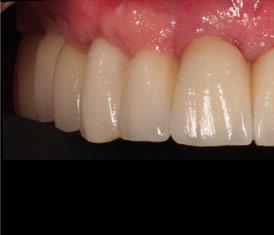

A los 4 meses, se retiró la prótesis provisional, verificando la